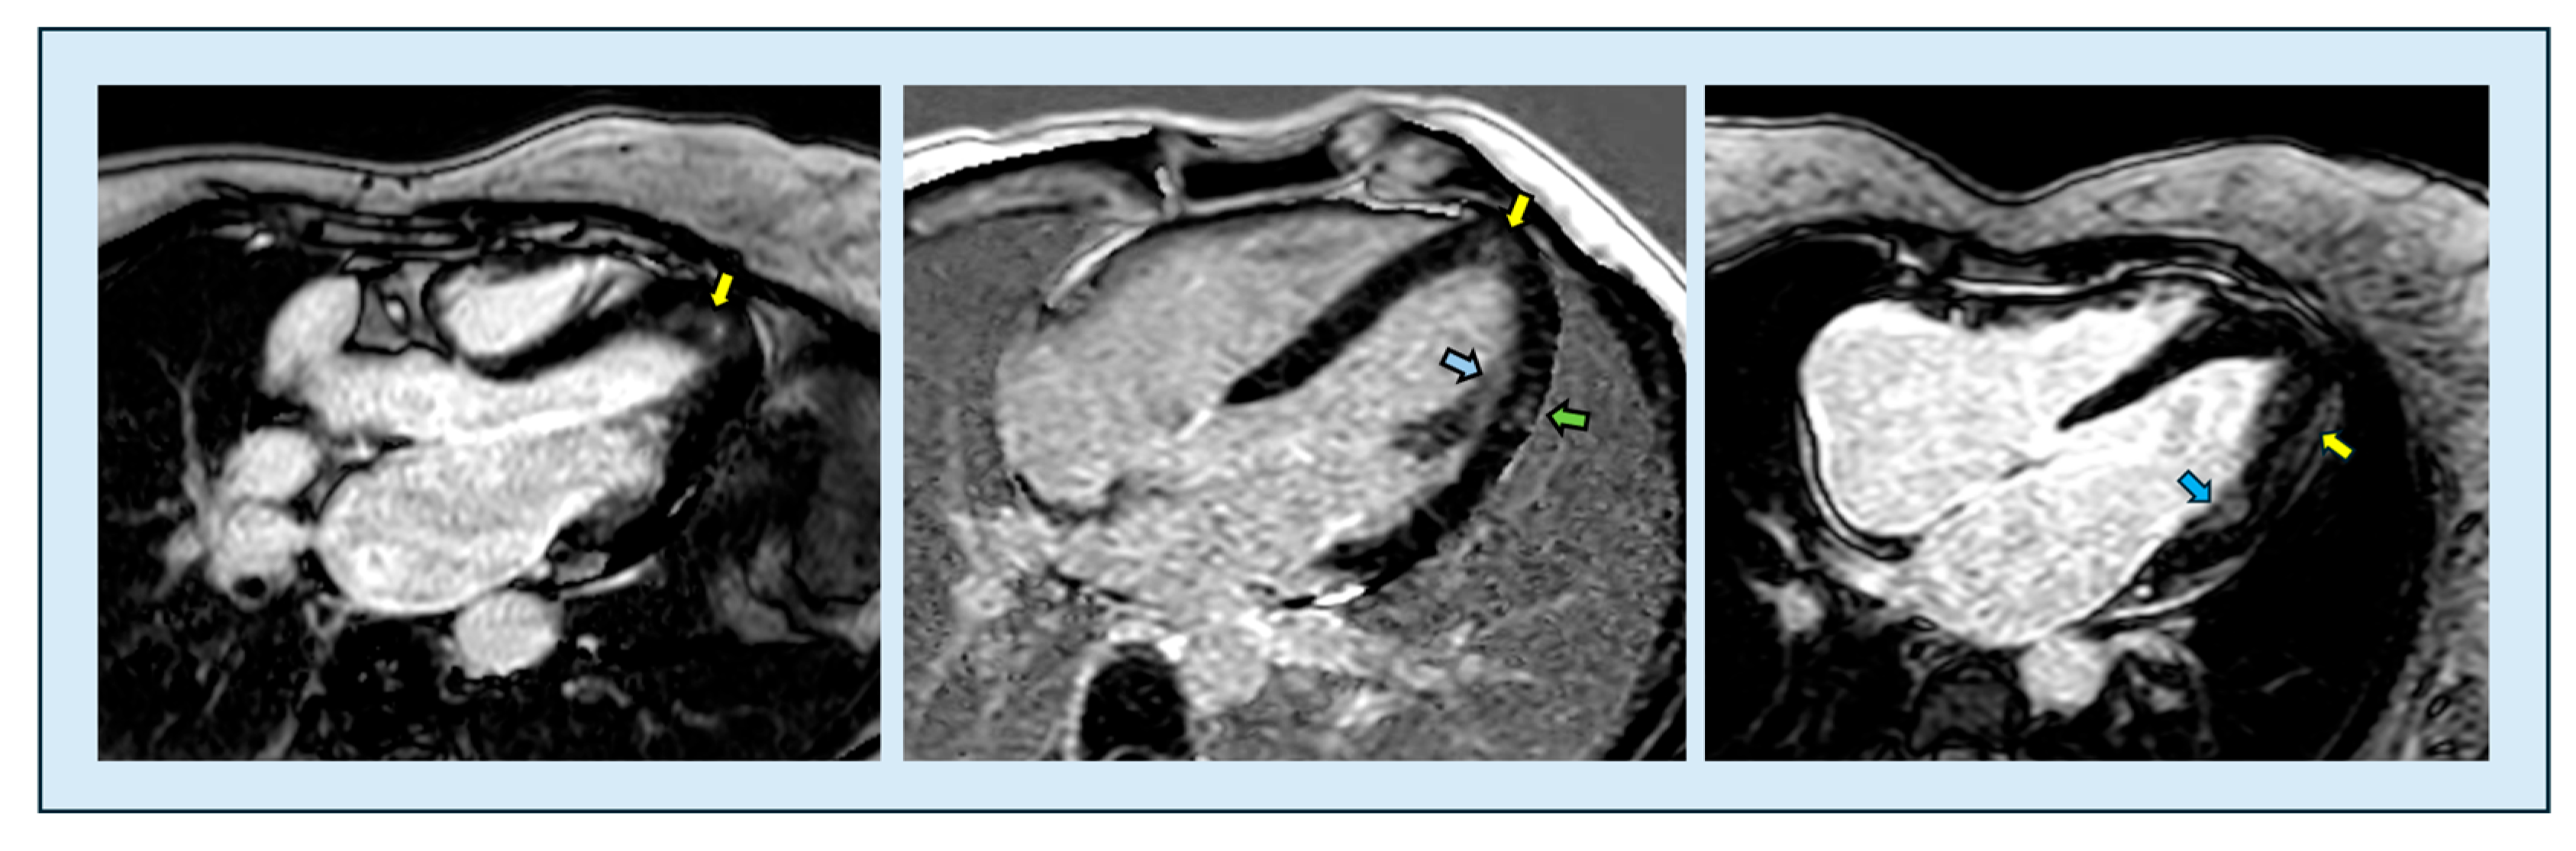

6.3.3. Late Gadolinium Enhancement

- Liu, J.; Zhao, S.; Yu, S.; Wu, G.; Wang, D.; Liu, L.; Song, J.; Zhu, Y.; Kang, L.; Wang, J.; et al. Patterns of Replacement Fibrosis in Hypertrophic Cardiomyopathy. Radiology 2022, 302, 298–306. [Google Scholar] [CrossRef]

- Chan, R.H.; Maron, B.J.; Olivotto, I.; Pencina, M.J.; Assenza, G.E.; Haas, T.; Lesser, J.R.; Gruner, C.; Crean, A.M.; Rakowski, H.; et al. Prognostic value of quantitative contrast-enhanced cardiovascular magnetic resonance for the evaluation of sudden death risk in patients with hypertrophic cardiomyopathy. Circulation 2014, 130, 484–495. [Google Scholar] [CrossRef]

- Chiribiri, A.; Leuzzi, S.; Conte, M.R.; Bongioanni, S.; Bratis, K.; Olivotti, L.; De Rosa, C.; Lardone, E.; Di Donna, P.; Villa, A.; et al. Rest perfusion abnormalities in hypertrophic cardiomyopathy: Correlation with myocardial fibrosis and risk factors for sudden cardiac death. Clin. Radiol. 2015, 70, 495–501. [Google Scholar] [CrossRef] [PubMed]